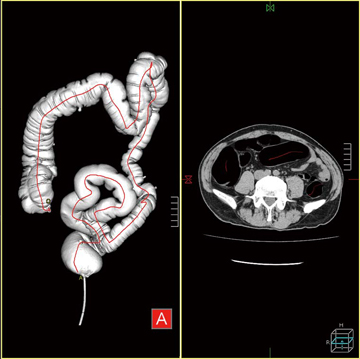

解析する画像データの読み込みを行うと,腹部の空気領域が自動的に抽出され三次元画像として表示される。大腸部分には,観察経路となる芯線が設定される(図4)。芯線領域抽出ボタンを押すことで,小腸など観察に不必要な部分が取り除かれ,大腸部分のみを表示させることができるため大腸の走行や狭窄部位の有無などの観察が容易となる(図5)。

図4 芯線設定画面 |

図5 芯線抽出画像 |